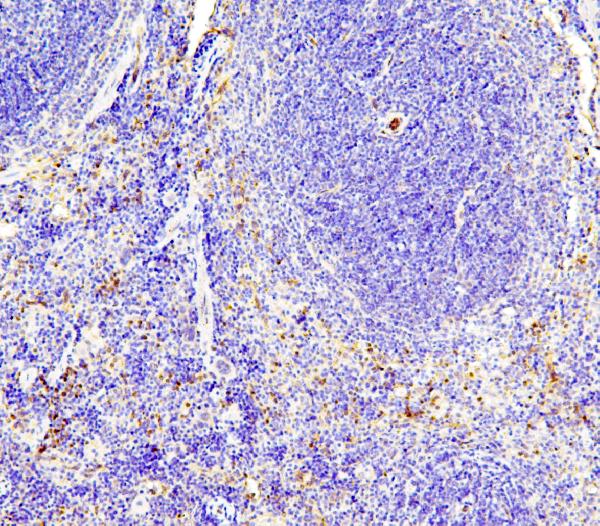

IHC analysis of eNOS/NOS3 using anti-eNOS/NOS3 antibody (A01604-2).

eNOS/NOS3 was detected in a paraffin-embedded section of rat spleen tissue. Biotinylated goat anti-rabbit IgG was used as secondary antibody. The tissue section was incubated with rabbit anti-eNOS/NOS3 Antibody (A01604-2) at a dilution of 1:200 and developed using Strepavidin-Biotin-Complex (SABC) (Catalog # SA1022) with DAB (Catalog # AR1027) as the chromogen.